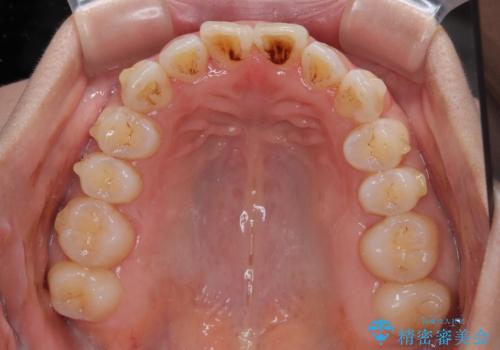

【モニター】飛び出した上顎前歯 補助装置を併用したインビザライン矯正治療

- 上下前歯が非接触となり、前方に突出していることを気にして来院された患者様です。

上下の前後差が大きいため、インビザライン単独での上顎歯列移動は困難と判断し、補助装置により上顎歯列を後方移動させ、その後インビザラインにて仕上げていくこととしました。

また、舌の突出癖が非接触の原因の大きな要因と考えられるため、舌のトレーニングをしっかり行っていくよう指導しました。